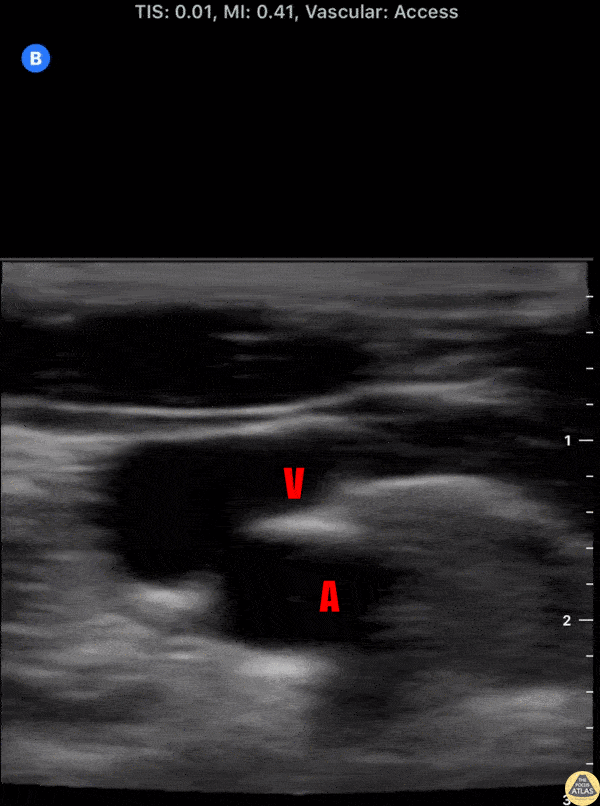

Localization and view of the brachial plexus nerve roots (*) in the interscalene groove. The right of screen is anterior/medial and left of screen is lateral/posterior. The carotid artery (A) and internal jugular vein (V) can be seen anterior and medially to the brachial plexus. Dr. Nick Aunchman University of Vermont Medical Center